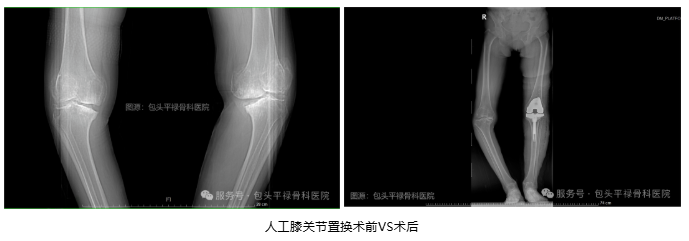

顾名思义,是指通过手术将受损的膝关节部分或全部替换为人工关节,以恢复关节功能、缓解疼痛和改善生活质量。医生会移除严重磨损的关节部位,在原位安装上与原始膝关节表面形状类似的假体,使用骨水泥使假体与患者自身的股骨和胫骨固定在一起,从而恢复膝关节的正常功能。